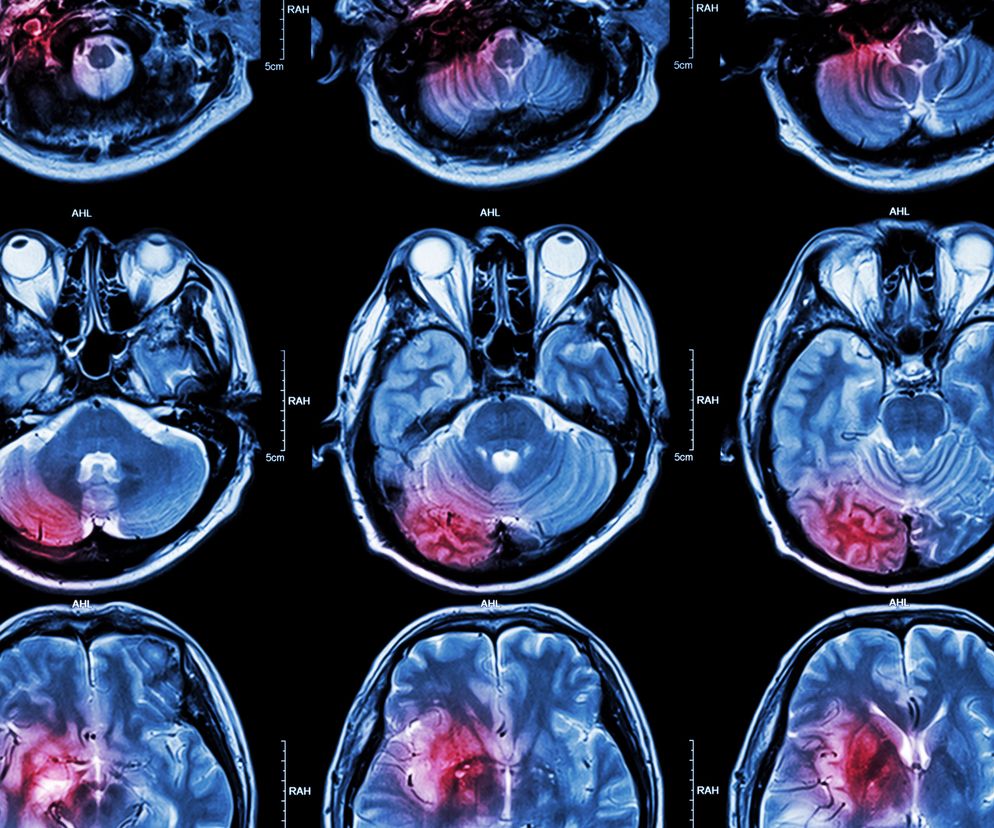

Udar mózgu - diagnostyka

Pacjent z udarem mózgu powinien trafić jak najszybciej na oddział neurologiczny, dysponujący tomografem komputerowym, aby w ciągu kilku godzin otrzymać specjalistyczną pomoc. Badanie tomograficzne jest niezwykle ważne, ponieważ pozwala zobaczyć obszar mózgu dotknięty choroba i określić jej rodzaj. Jeśli nie można wykonać tomografii, robi się punkcje lędźwiową, czyli pobiera specjalną igłą płyn mózgowo-rdzeniowy.

USG dopplerowskie pozwala ocenić stan tętnic szyjnych, które mogą być zablokowane przez zator. Sprawdza się również poziom krzepliwości krwi.

Jeżeli chory jest przytomny, wykonuje się też badanie neurologiczne (sprawdza się poprawność odruchów, ocenia siłę i sprawność mięśni, bada reakcje źrenic na światło). To wszystko pozwala precyzyjnie wyznaczyć obszar zniszczenia mózgu.

Na szpitalnym oddziale rehabilitacji neurologicznej (udarowym) pacjent jest poddawany szeregowi badań i testów, takich jak tomografia komputerowa (CT) czy rezonans magnetyczny (MRI), aby uzyskać jak najwięcej informacji na temat jego stanu zdrowia.